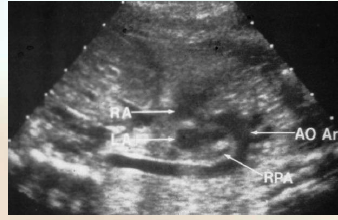

what is this?

aortic arch and branches

looks like a candy cane

what is speciat about these veiws of the <3 ?

Left Ventricular Outflow Tract – AKA Aortic root or 5-Chamber view

Right Ventricular Outflow Tract

what does the left ventricular outflow tract (LVOT) demonstrate?

continuity of the interventricular septum to the aortic root

what does the rt ventricular outflow tract (RVOT) demonstrate?

Demonstrates main pulmonary artery